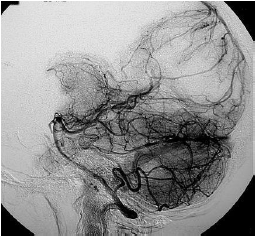

A angiotomografia digital cerebral demonstra a fase